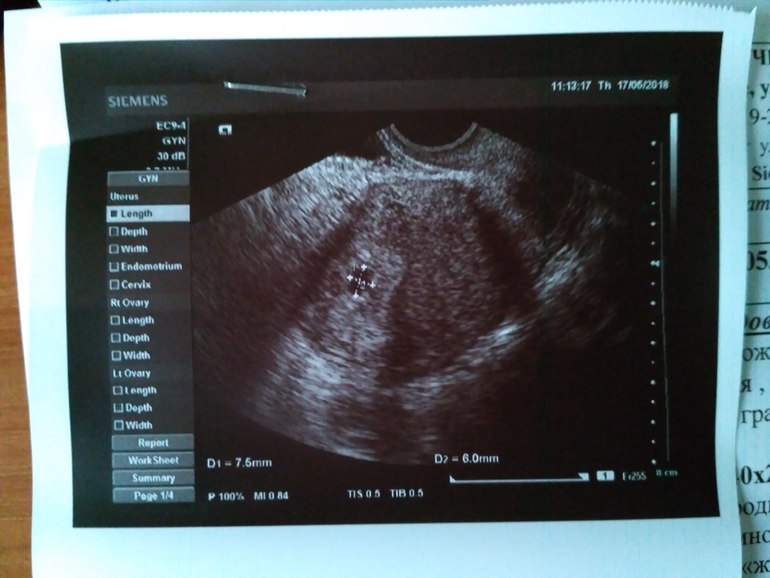

Да) Вот бусинка. 5-6 недель)